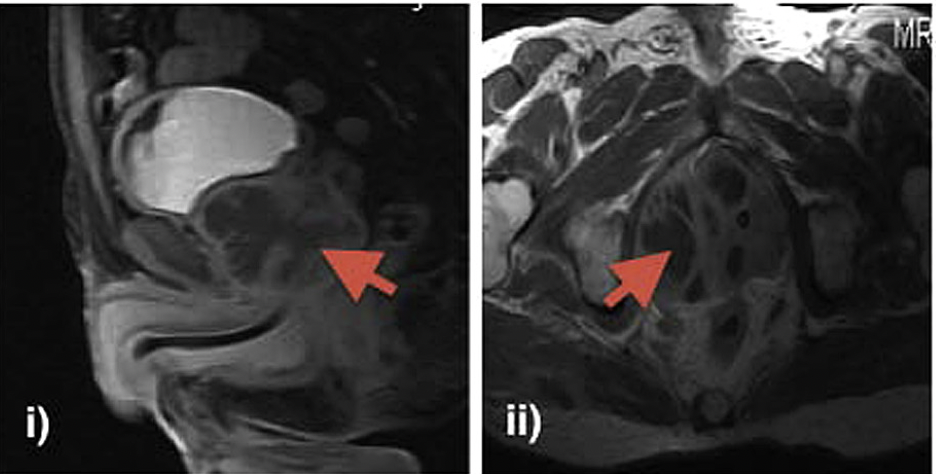

A prostatic abscess is an uncommon urological emergency, but it is a serious infection of the prostate with a high mortality rate unless properly treated. Patients with diabetes mellitus, renal insufficiency, and immune suppression are particularly at risk. Urethral catheterisation, lower urinary tract instrumentation, and a prostate biopsy are among the possible predisposing factors. Once liquefaction and abscess formation are diagnosed, several approaches have been described for drainage. Open perineal drainage, transurethral deroofing, transrectal needle aspiration, or tube drainage, and percutaneous drainage are the main therapeutic options. #abscess #turp #prostate